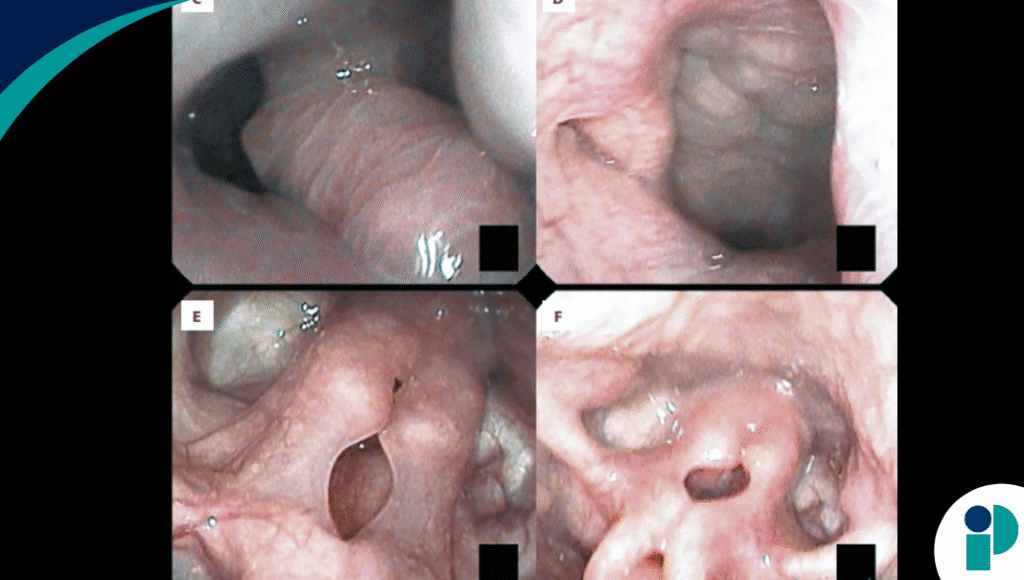

La evaluación clínica detallada reveló características asociadas al síndrome como microcefalia y rasgos faciales toscos, pero las imágenes médicas (tomografía computarizada y resonancia magnética) identificaron una masa de tejido blando nasofaríngea y edema de cuerdas vocales. La nasofaringoscopia con fibra óptica confirmó disfunción bilateral de las cuerdas vocales y laringomalacia.

La paciente fue sometida a una intervención quirúrgica compleja que incluyó la resección de las masas nasofaríngeas y de la base de la lengua, junto con una supraglotoplastia. El estudio histopatológico de las masas resecadas confirmó que se trataba de hamartomas, crecimientos benignos y desorganizados de tejido.